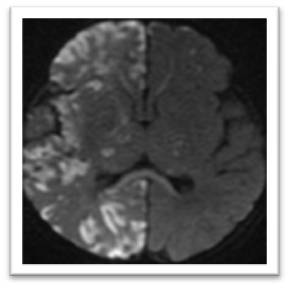

Primera gestación de madre sana, sin otros antecedentes de interés. Parto eutócico a las 39 semanas. Nace recién nacido con T. Apgar al minuto de 9 y a los 5 minutos de 10. A las 30h de vida realiza convulsiones tónicas de extremidades superiores. Destacaban la presencia de lesiones hipopigmentadas en extremidades inferiores distribuidas siguiendo las líneas de Blaschko. Se realiza RM cerebral a los 7 días (Figura 1 A y B).

La respuesta correcta es la 3. Lesión arterial isquémica multiterritorial cortico-subcortical derecha.

En el corte axial en DWI se aprecian lesiones isquémicas fragmentadas multi-territoriales cortico-subcorticales (como refiere la literatura) con predominio en nuestro caso en hemisferio derecho, afectando a los territorios tributarios de la arteria cerebral anterior, media y posterior. También se aprecian pequeñas lesiones isquémicas lacunares en ambos tálamos e hiperintensidad de señal en el esplenio del cuerpo calloso (probable degeneración pre-Walleriana). El estudio angio-TOF no mostró hallazgos significativos y la secuencia eco de gradiente (GRE) no mostró lesiones hipointensas que sugiriesen un origen hemorrágico.

Figura 1A. RM cerebral. Corte axial en DWI.